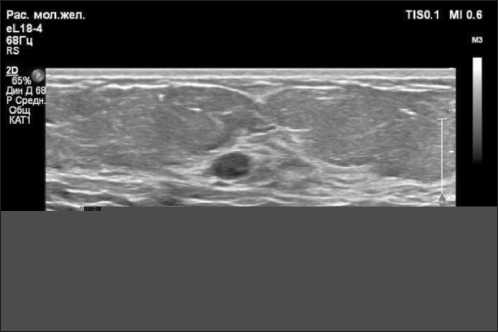

Рис. 5. УЗ-картина локализационной иглы в проекции опухоли. Примечание: рисунок выполнен авторами

Fig. 5. Ultrasound image of the needle’s location in the projection of the tumor. Note: created by the authors

Пациентке выполнена предоперационная разметка непальпируемого образования правой молочной железы с установкой локализационный иглы-проводника под УЗИ молочных желез и Rg-контролем (рис. 5, 6). В I онкологическом отделении Онкологического центра № 1 ГБУЗ «ГКБ им. С.С. Юдина ДЗМ» 13.08.24 выполнена секторальная резекция правой молочной железы. Интраоперационный вид удаленного сектора правой молочной железы с опухолью и локализационной иглой-проводником представлен на рис. 7.